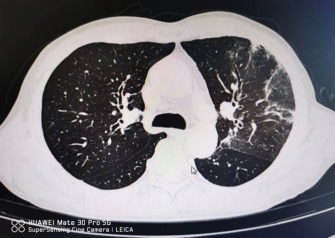

近日,常德市第二人民医院感染科成功救治了一例鹦鹉热肺炎的患者。60岁的李伯伯因突发双耳听力下降,来到常德市第二人民医院就诊,接诊医生仔细询问病史及生命体征监测,发现患者已反复高热10余天,精神极差。立即安排肺部CT检查并邀请感染科医生会诊。影像报告提示患者存在肺炎,且考虑鹦鹉衣原体可能。感染科医师详细询问患者,患者虽无饲养鹦鹉、鸽子等情况,但有饲养鸡鸭,且卫生条件极差。根据流行病学史、临床表现及影像学资料,高度提示患者存在鹦鹉热肺炎的可能,病情较重,遂转入感染科进行更全面、更深入的治疗。

患者入院时的影像资料